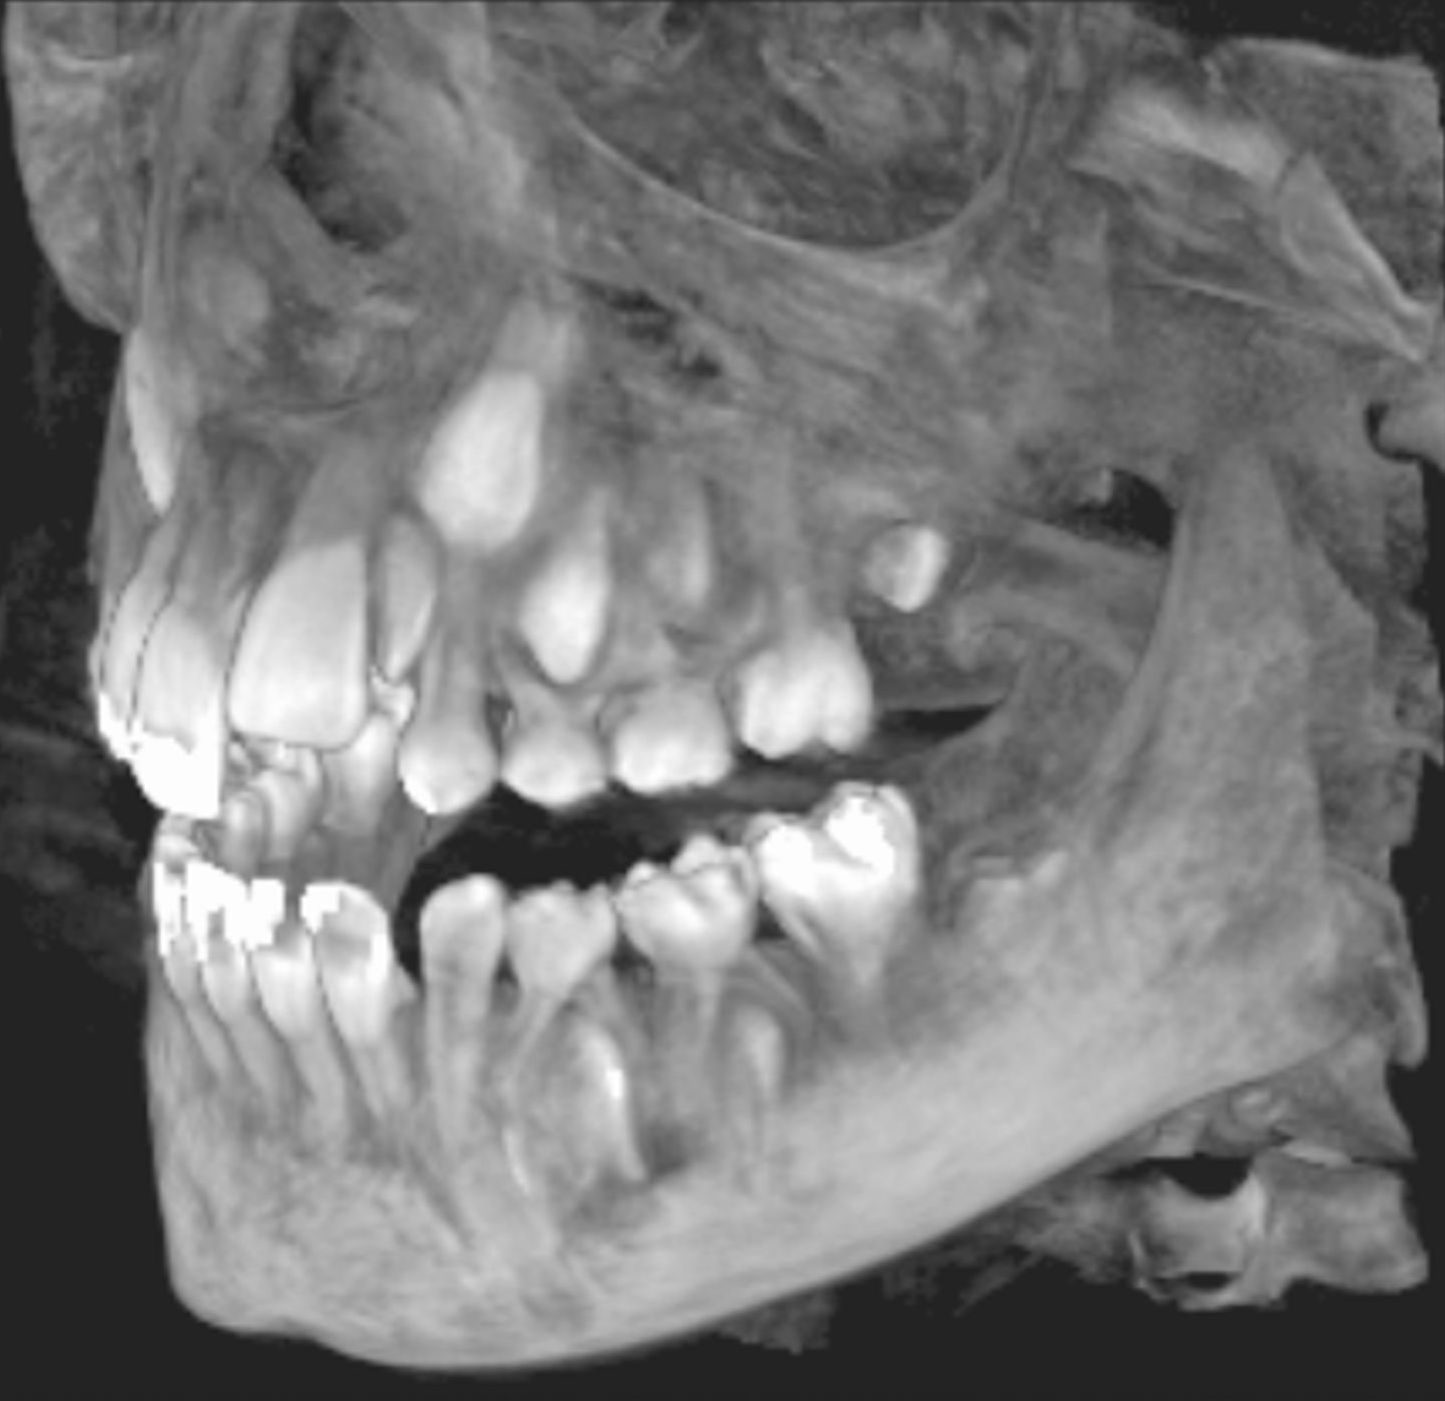

Les nouvelles générations de scanner permettent de faire une acquisition d’un volume global d’une partie du corps et de travailler à l’intérieur de ce volume en isolant une structure anatomique donnée et de l’explorer dans tous les plans de l’espace.

Grace à la technique de seuillage il est possible de dissocier progressivement les dents des structures osseuses environnantes dans le volume donné.

Le cone beam est une nouvelle technique de radiographie numérisée situé entre le panoramique dentaire et le scanner, il utilise un faisceau d’irradiation de forme conique d'où son nom. Cet appareil présente notamment l’avantage d’être plus précis que le panoramique dentaire et il possède une résolution similaire, voire supérieure à celle du scanner, avec en plus la possibilité d’une reconstruction numérique en 3D.

Il évalue au plus juste le volume osseux et la position des structures anatomiques comme les nerfs en vue de la pose d’implants. La modélisation en 3D permet la taille et la forme des implants proportionnellement à la morphologie du patient et de simuler virtuellement leurs emplacements.